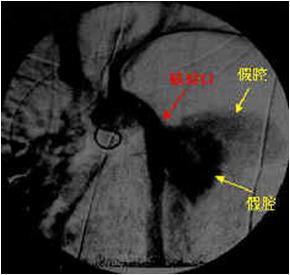

胸主动脉增强CT造影红箭头示主动脉弓破口处:

在MPR, CPR图象中,主动脉夹层的真假腔显示不同密度,真腔明显强化,真腔小而假腔大,真腔明显受压变窄,可见低密度血栓。